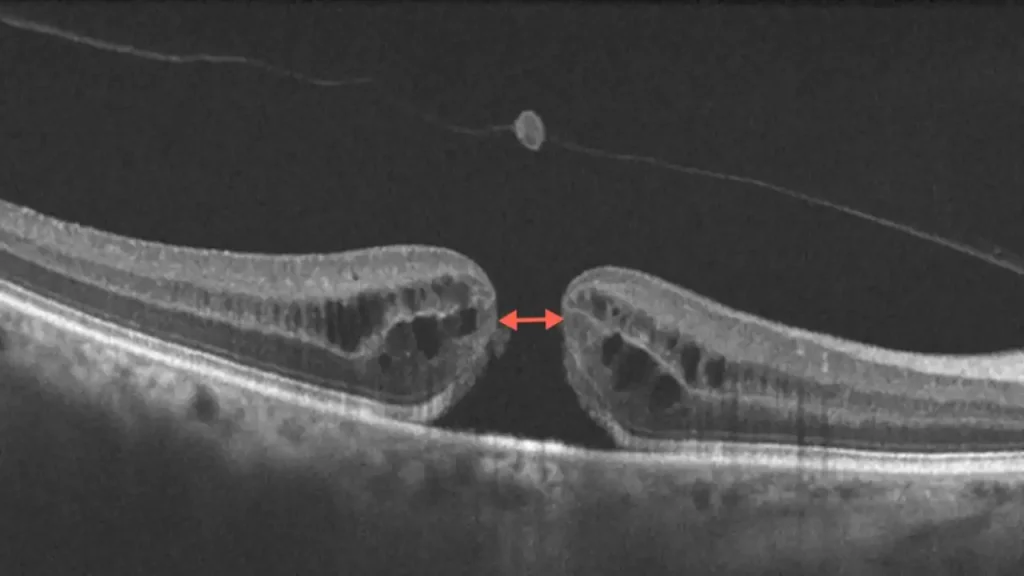

Sudomotor dysfunction may be an early detectable abnormality in diabetic small fiber neuropathy. The aim of this study was to evaluate the efficacy of Sudoscan™ (Impeto Medical, Paris, France) in detecting diabetic neuropathy (DN), in comparison with other standardized tests, in patients with diabetes mellitus (DM).

اختلال عملکرد سودوموتور ممکن است یک ناهنجاری قابل تشخیص زودهنگام در نوروپاتی فیبر کوچک دیابتی باشد. هدف از این مطالعه ارزیابی اثربخشی Sudoscan™ (Impeto Medical، پاریس، فرانسه) در تشخیص نوروپاتی دیابتی (DN)، در مقایسه با سایر آزمایشهای استاندارد، در بیماران مبتلا به دیابت شیرین (DM) بود.